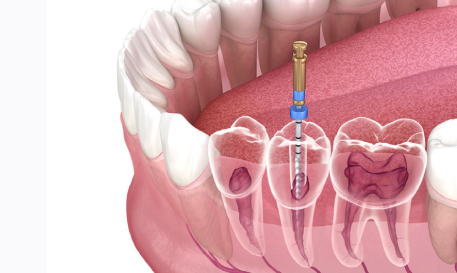

Root Canal Treatment

Removes infection from the affected tooth safely and effectively. Helps preserve and protect your natural tooth structure. Prevents the spread of infection to surrounding tissues. Restores full chewing strength and daily function. Reduces pain and discomfort caused by deep decay. Promotes long-term oral health and tooth stability. Ensures a comfortable and reliable solution for lasting relief.